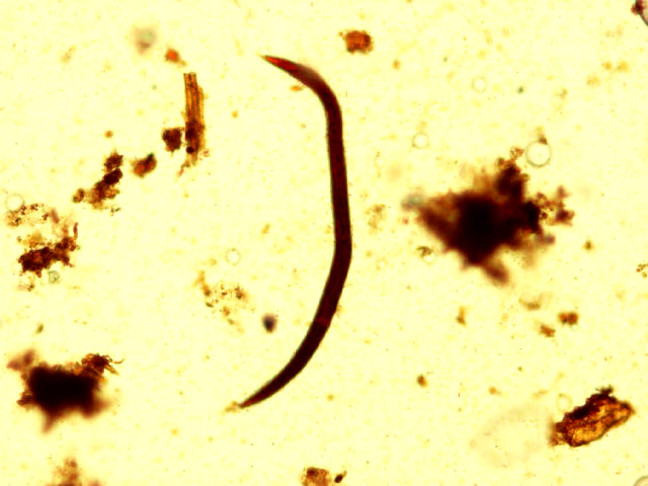

- 40x

Stongyloides

Notice how the larvae are normally curved